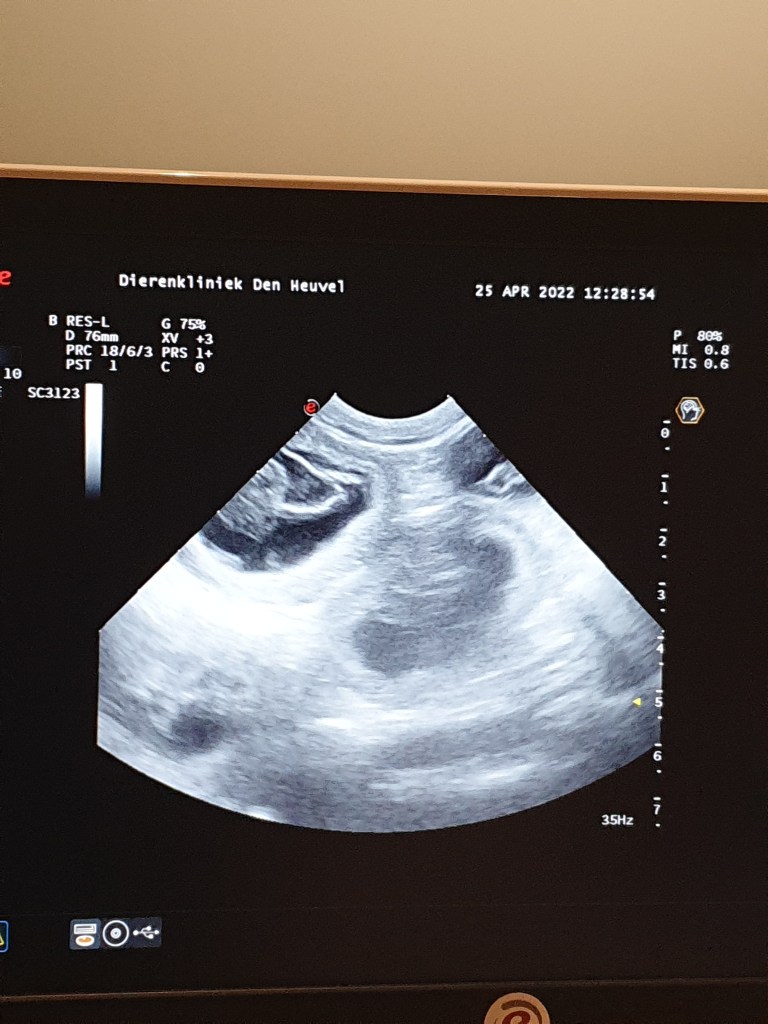

25 april 2022

25 maart 2022

Echo van Nova…

Ze is zwanger!!!26 mei 2022